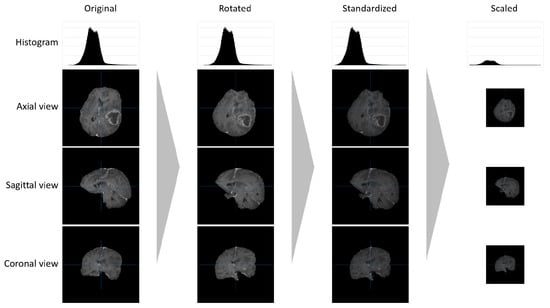

2.1. Data Pre-Processing